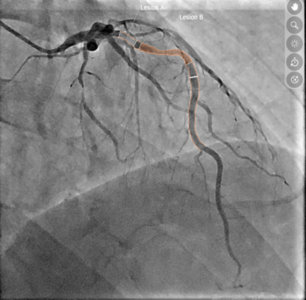

Links die klassische Darstellung, rechts das KI-Modell: Mit Hilfe der Software konnten zwei Engstellen an der Vorderwand des Herzens identifiziert und eine relevante Beeinträchtigung der Sauerstoffversorgung festgestellt werden. Das hämodynamische Modell zeigt: Eine gezielte Aufdehnung nur einer der beiden Stenosen reicht aus, um den Blutfluss wieder zu normalisieren.